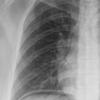

RML collapse

(see previous image)